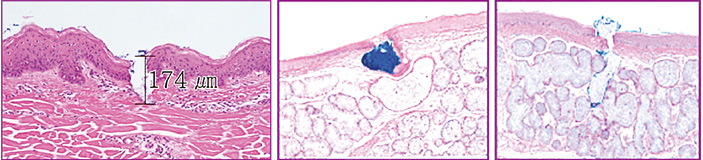

再生因子が最も効果を発揮するのは真皮内と言われており、オスモインジェクターはその真皮層に薬液を確実に届けるための注入機器です。

容器と針が一緒になっており、薬液を容器に入れ針を皮膚に押し付けると、薬液が自動的に真皮内に注入されていきます。

針は超極細の40Gが採用されており、使用時の痛み、出血はほとんどありません。

また必要以上に肌を傷つけないため、ダウンタイムもないという理想的な注入装置といえます。

その最大の特徴は、針のスパイラル構造であり、40Gというきわめて細い針でもしっかりと薬液を真皮内に届けることができます。

※オスモインジェクター使用時の皮膚の組織像